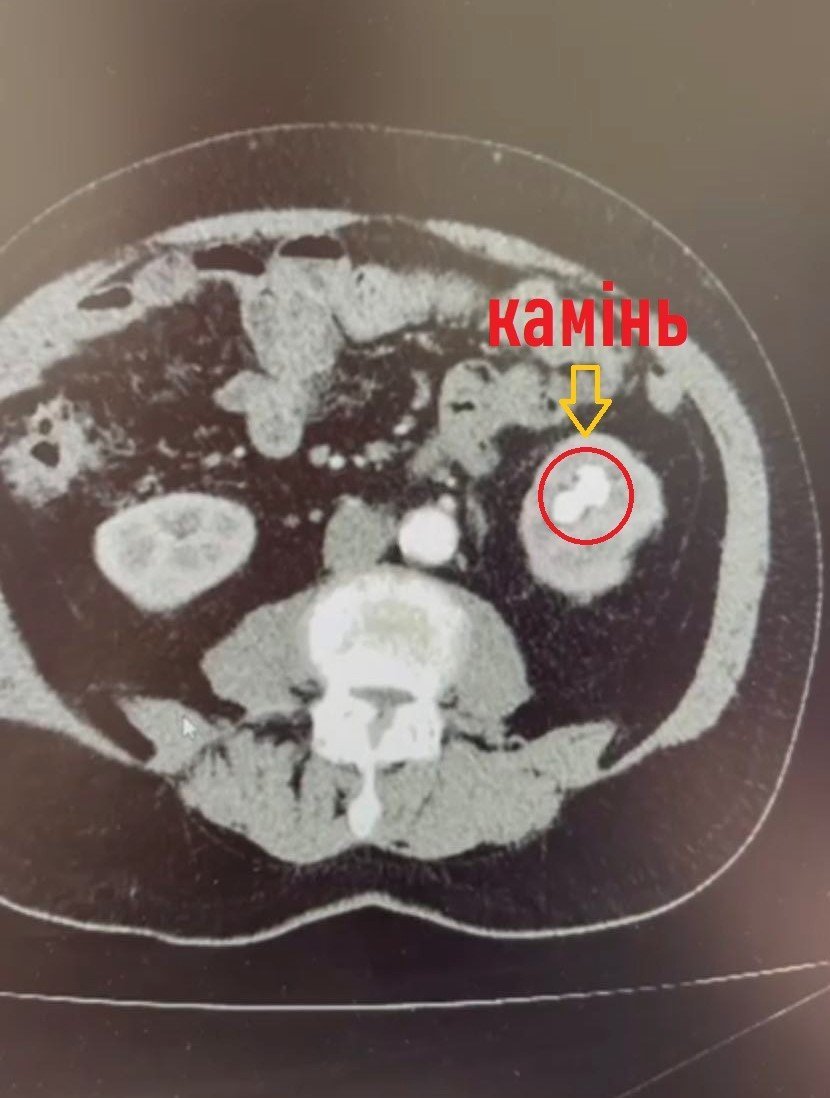

Обстеження на комп’ютерному томографі показали наявність в нирці коралоподібного каменя розміром 38х28 мм та доброякісного пухлинного утвору до 3 см в діаметрі з неоднорідним кровотоком у центрі, який знаходився на судинній ніжці лівої нирки.